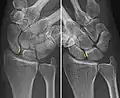

Complete rupture of this ligament leads to wrist instability. The main type of such instability is dorsal intercalated segment instability (DISI) deformity, where the lunate angulates to the posterior side of the hand.[4][5]

A dynamic scapholunate instability is where the scapholunate ligament is completely ruptured, but secondary scaphoid stabilizers are still preserved;[6] these are the scaphotrapezial (ST), scaphocapitate (SC) and radioscaphocapitate (RSC) ligaments.[6] In a static scapholunate instability, these other ligaments are ruptured as well.